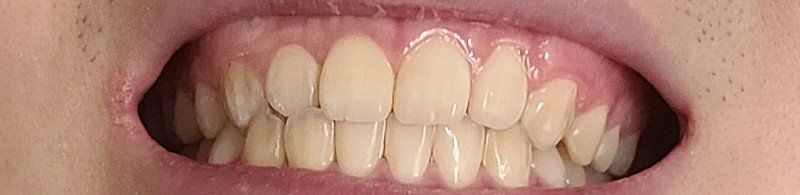

2.앞니도 윗니가 아랫니를 포개긴 하는데 사이 공간없이 딱붙긴해요 원래 살짝 띄워져야하나요?

• 3번 째 사진

2.앞니도 윗니가 앞으로 나오는 것이 정상입니다. 사진에서는 윗니가 앞으로 나온 양이 적기는 하지만 정상 범주입니다.